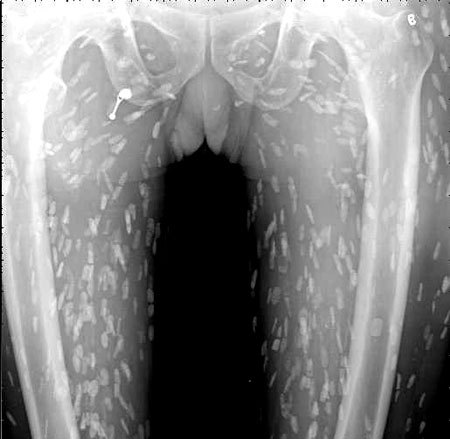

엑스레이를 찍어보니, 온몸에 촌충 같은 기생충이 퍼져있는 것이 Xray사진에 찍혔다.

기침으로 인한 고통을 호소한 환자를 진료하던 의료진은 환자의 엑스레이 사진을 보고 경악했습니다. 엑스레이 촬영물에는 여러 마리의 촌충과 유충이 가득 찍혀있는 것이었습니다.